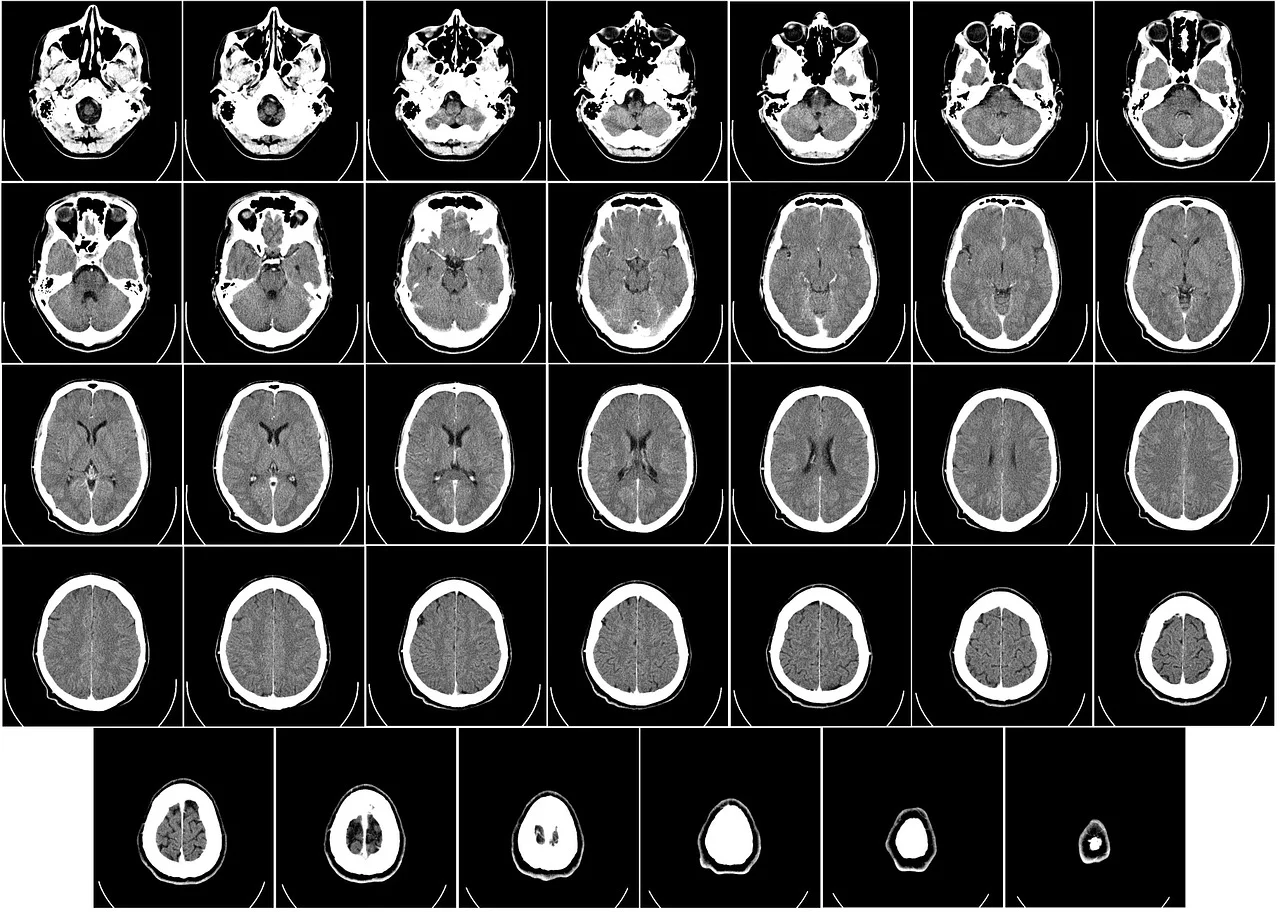

- 정기검진 – 40대 이상은 뇌 MRI, CT 등을 통한 조기 진단이 필요합니다.